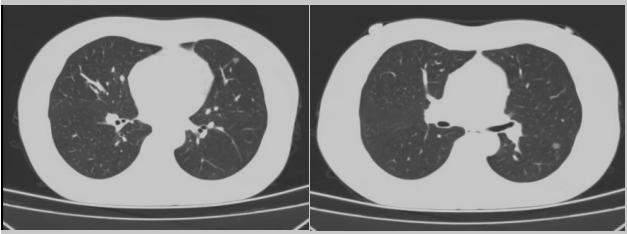

病例二:42歲的范女士,半年前體檢時(shí)發(fā)現(xiàn)雙側(cè)多發(fā)肺結(jié)節(jié),平時(shí)沒(méi)有什么不適。四個(gè)月后再次復(fù)查胸部CT,左上肺及下肺多發(fā)的磨玻璃結(jié)節(jié),其中下葉9mm的結(jié)節(jié)定為高危病灶。看到結(jié)果范女士坐不住了,多方打聽慕名找到了市二院院長(zhǎng)王瑾,經(jīng)“肺結(jié)節(jié)MDT”團(tuán)隊(duì)會(huì)診后,決定手術(shù)治療。入院后,胸外科副主任醫(yī)師薛飛詳細(xì)與范女士溝通,并利用Mimics做好了術(shù)前肺部三維重建手術(shù)規(guī)劃,打消了范女士心中的顧慮。經(jīng)過(guò)前期充分準(zhǔn)備后,歷經(jīng)1小時(shí)30分,完成“胸腔鏡下左肺上葉舌段楔切及左肺下葉背段切除術(shù)”,術(shù)后病理檢查結(jié)果確診為左肺微浸潤(rùn)性腺癌。在胸外科團(tuán)隊(duì)的悉心照顧下,患者術(shù)后恢復(fù)良好,一周后順利出院。